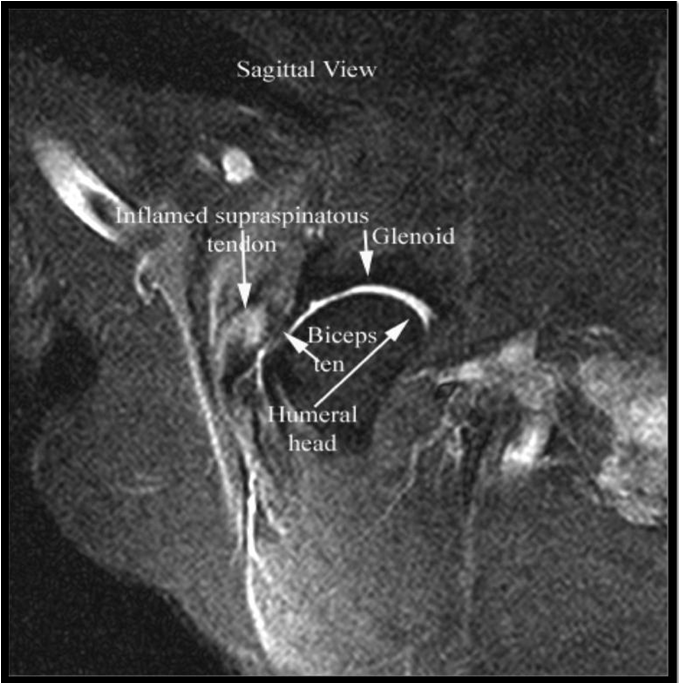

Results: Dogs aged 4 months to 14 years (average 6.5 years; median 6 years) were diagnosed with ST. Performance and sporting dogs were 39.4% of the population, with 58.1% of them being agility dogs. Pain was elicited on palpation of the supraspinatus tendon in 49.3% of dogs. Shoulder radiographs in 283 dogs showed mineralisation in 13% of cases. MRI of the shoulder was performed in 31 cases and revealed findings indicative of ST, including hyperintensity of signal on T1 weighted image (or “spin-lattice”) and Short T1 Inversion Recovery (STIR) sequences of the supraspinatus tendon at its insertion on the greater tubercle and mineralisation of the supraspinatus tendon. Common ultrasonographic findings included increased tendon size (76%), irregular fibre pattern (74%), and non-homogeneous echogenicity (92.5%). The most common findings on shoulder arthroscopy were supraspinatus bulge (82.2%) and subscapularis pathology (62.4%). Elbow pathology was recorded in 54.5% of dogs. Treatment outcomes showed 74.6% of dogs failed to respond to non-steroidal anti-inflammatory drugs (NSAID) and 40.8% failed to respond to rehabilitation.